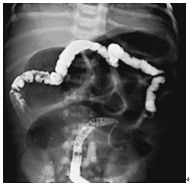

49. 一個十天大的早產兒,出生後有胎便解出,但在第四天大時陸續開始出現餘奶,這兩天發現有腹脹嘔吐的現象,且嘔吐物為綠色膽汁性。目前體重較出生體重少了15%。腹部x光如圖。以下敘述,何者不正確? (A)此早產兒患了壞死性腸炎(Necrotizing enterocolitis, NEC)。 (B)應先置放鼻胃管引流,除可減輕腹壓,也可減少吸入性肺炎的發生。另外,必須給予足夠的水分以補充體液的流失。 (C)可以考慮使用Gastrografin診斷及治療。 (D)若確定有腸穿孔,應會診小兒外科醫師考慮手術治療。 (E)可能和cystic fibrosis的患者有相關。